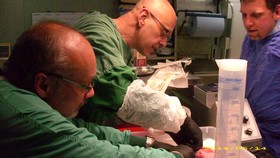

| Am

12.11. 2014 testete das Ulmer Kompetenzteam in Gegenwart von Michael

Wagner (DGAB-Vorsitzender) und Karen Conrad - welche im medizinischen

Bereich arbeitet - eine auf das Gehirn zentrierte Perfusionsmethode

mit auf 0°C gekühlter 75%iger

Vitrifikationslösung VM1 am Körper

eines vor etwa 24 Stunden Verstorbenen, der sich der medizinischen

Wissenschaft vermacht hatte. Solche Versuche sind interessant für die Testung von gerinnungs- hemmenden Mitteln und des postmortalen Verschlusses von Gefäßen, sowie die Erhaltung von überlebenden Zellen u.a. für die Alzheimer Forschung. Die Perfusion wurde nach medianer Sternotomie sowie Eröffnung und Spreizung des Thorax über eine arterielle Kanüle in der aufsteigenden Aorta und eine venöse Kanüle in der Vena cava superior als extrakorporaler Kreislauf angelegt. Durch Unterbindung der Armarterien beiderseits und Abklemmen der Bauchaorta wurde die Lösung über den Kopf geleitet. Der Kreislauf wurde von einer Rollerpumpe betrieben. Das System lief regelrecht, jedoch konnte der Rückfluss aus der oberen Hohlvene nur durch einen Wasserstrahlbetriebenen Sog erreicht werden. Ein Fluss im geschlossenen Kreislauf wurde aufgegeben, da sich so lange nach dem Ableben sehr viele Gerinnsel in der Lösung befanden. Frau Conrad schlug vor, zu versuchen ob Heparin entgegen der Theorie den Abgang der Thromben steigert (es werden immer wieder Erfahrungen in dieser Richtung diskutiert). Es wurden 35000 IE Heparin eingeführt. Es bestand der Eindruck, dass der Rückfluss sich dadurch etwas besserte. Wie zu erwarten trat eine pralle Konsistenz an Gesichtshaut und Hinterkopf auf, welche die selektive Kopf Perfusion bestätigte. Nach Entfernung der Klemmen und Kanülen wurde der Thorax verdrahtet und die Hautwunde geschlossen. Der Versuch dauerte drei Stunden. |

| Die Geräte – noch nicht einsatzfähig – : unten Frostschutzreservoir, oben (mit blauem Deckel) das Mischreservoir, dahinter die Pumpe und im Hintergrund an einem Ständer die Bedienungselemente der Säge. |